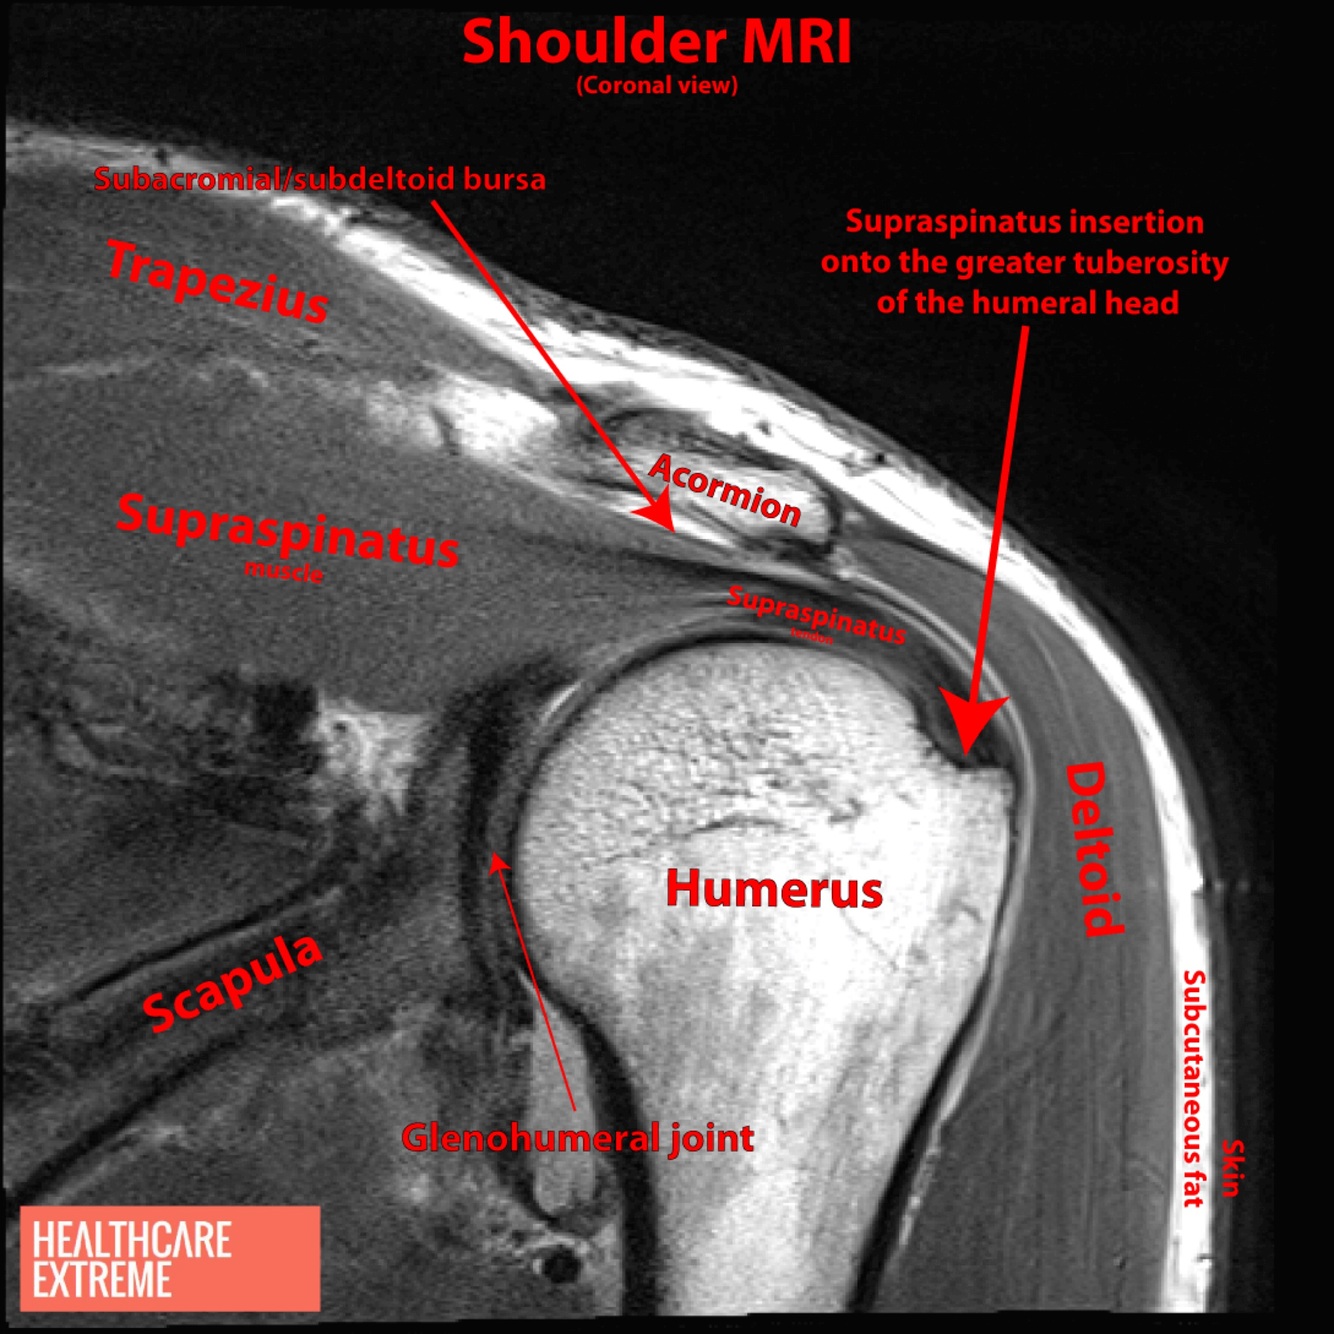

Hiperintenso en T2

Detecta lesiones asociadas y desgarros pequeños

A

RM manguito rotador

Normal

Desgarro del manguito